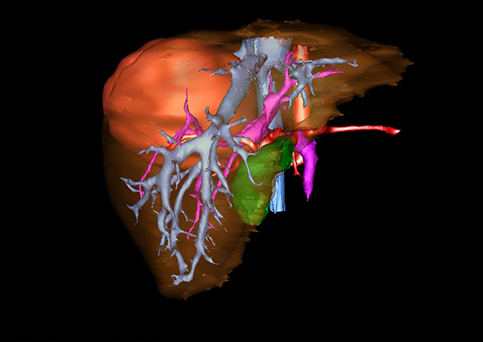

图1 位于肝右的叶肝母细胞瘤, 6个月,男婴

目前常用的检查方法有B超检查、CT、MRI、血管造影等。与其它的腹部肿块的诊断不同,对于小儿肝母细胞瘤血管造影具有重要的意义,可以作为手术前介入治疗的手段,也可为手术提供非常有效的影像学指导,但技术要求高,操作较复杂,且给患儿带来一定的痛苦。近年借助计算机辅助手术系统进行CT原始影像三维重建、手术规划和计算机虚拟手术技术,为精准肝脏手术提供了极为有效的技术支持。

近年来由于数字医学的发展,基于可视化三维重建技术的计算机辅助手术系统极大推进了小儿肝脏肿瘤的精准手术的进步。可以立体透视肝脏解剖、精确掌握肝段的边界、精确测算肝段乃至任意血管所支配的功能体积、准确定位病灶及其与邻近血管的解剖关系,最终对不同手术方案进行比较、筛选和优化。因此,计算机辅助手术规划系统是实现精准肝切除的有力辅助工具,是未来数字外科、精准外科等21世纪外科新理念的重要技术支撑。

计算机辅助手术规划系统具有良好的操作可行性、计算准确性和三维显示效果,可半透明、交互式显示真实的肝内立体解剖关系和空间管道变异,准确计算肝内管道的直径、走行角度,两点间的垂直距离,和任意血管的支配或引流范围等传统二维影像无法获取的信息,有助于实施个体化手术,提高了手术的确定性、预见性和可控性。计算机辅助手术规划系统可直观显示预留肝脏的结构和功能,并可通过虚拟切割功能辅助术者对手术方案进行蹄选和优化,系统评估手术风险和制定对策,改变了部分二维规划的术式和切除范围,使部分二维规划认为不能切除的患者成功手术,提高了手术的根治性、安全性和病变的可切除性,更加符合精准肝脏外科的术前规划要求。详见第11章。